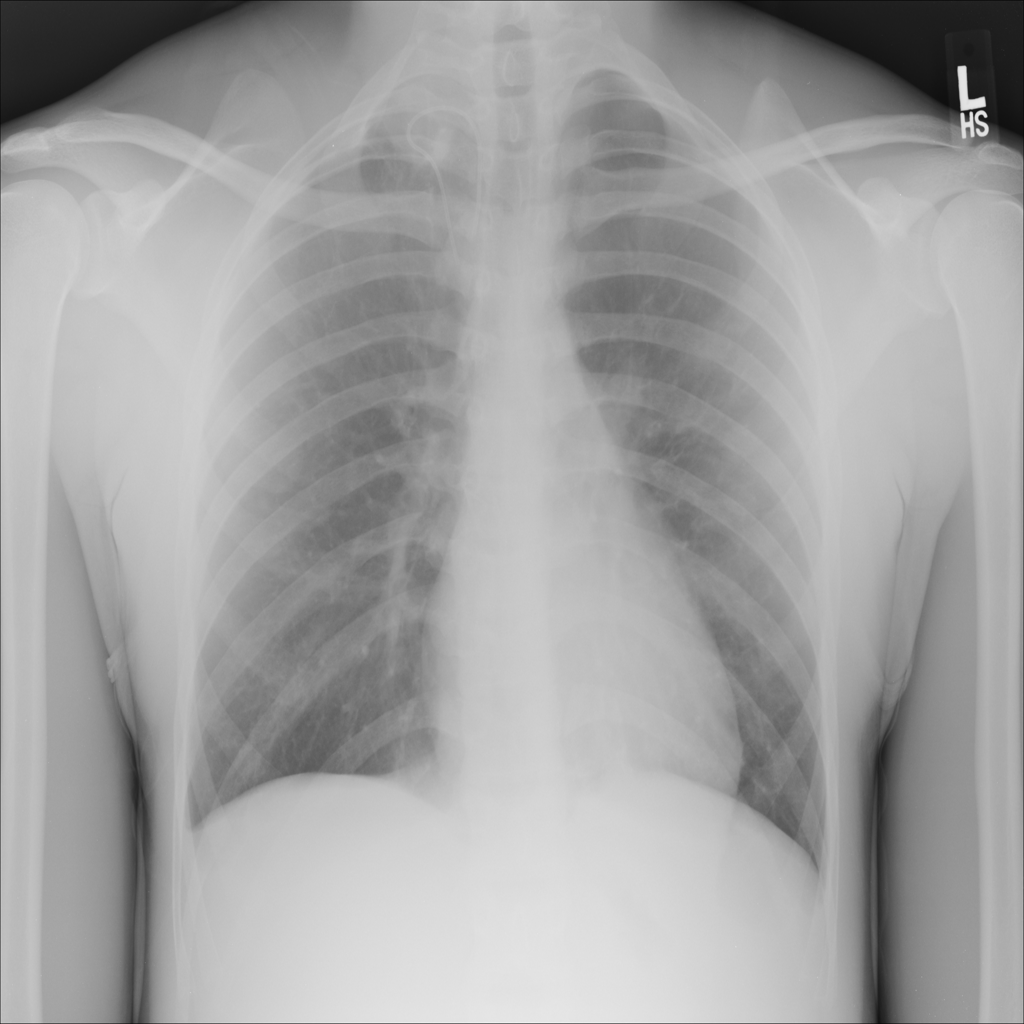

PAT-C0E5 · IMG-001Mass

PAT-C0E5 · IMG-001

PA